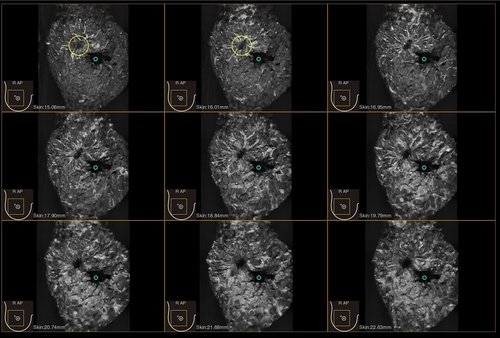

Das IBUS 60 ist ein intelligentes Brust-Vollvolumen-Ultraschallsystem der Marke SIUI.

Das IBUS 60 zeichnet sich durch Sicherheit und Komfort aus. Es bietet ein hochauflösendes Bild und reduziert somit Fehldiagnosen, was ideal für die Brustuntersuchung ist, insbesondere bei einer dichten Brust.

• Dreidimensionale Positionierung

• Nanopure Technologie zur Specklereduzierung